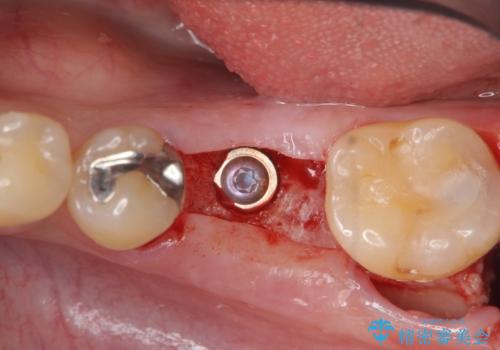

抜歯後ブリッジとインプラント治療を検討・相談し、より周囲の歯を削らずに済むインプラント治療を希望されたのでインプラントによる機能回復を計画します。

- 46.2万円(インプラント・チタンカスタムアバットメント・仮歯・ジルコニアクラウン)費用は治療当時の料金となります